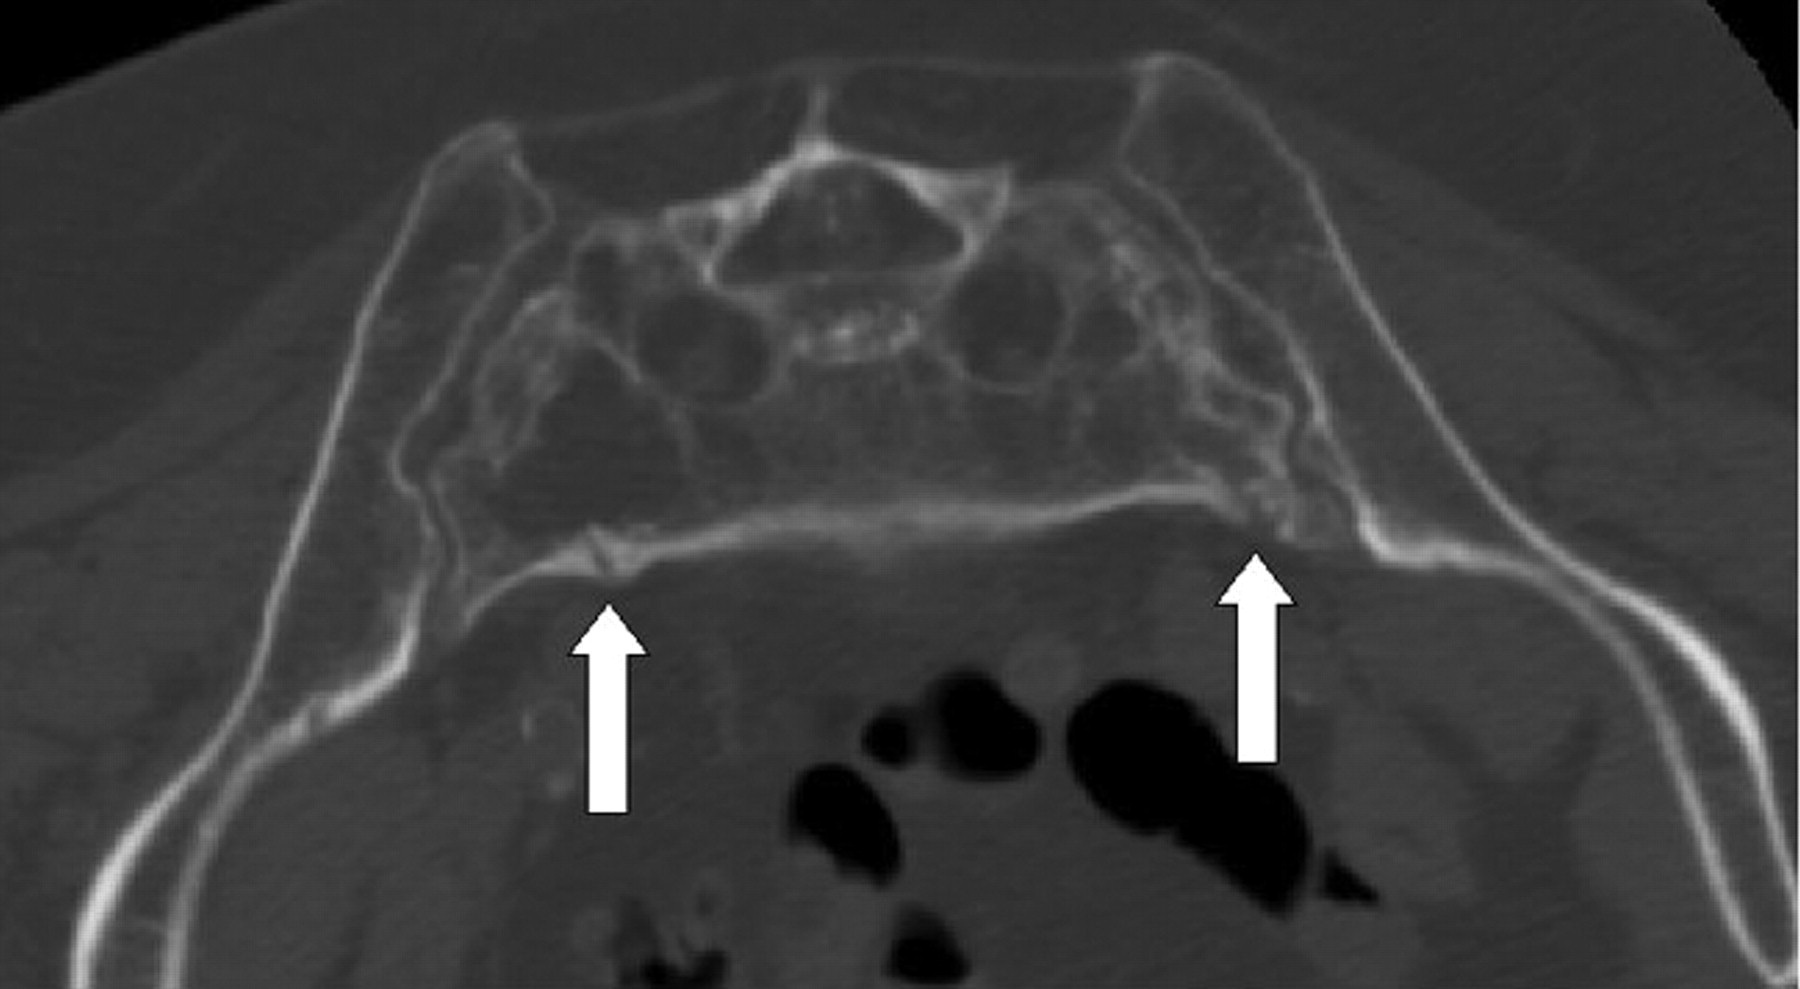

On neurologic examination, the patient was 157.5 cm (62 inches) and weighed 59 kg (131 lb). Neurologic examination was within normal limits. CT images of the lumbosacral spine demonstrated severe osteoporosis, sacroiliac joint incompetence, and bilateral comminuted fractures of the sacrum and pelvis (Fig 1). There was concern that lone sacroplasty would not provide adequate stabilization of her SIFs, and thus CT fluoroscopically guided percutaneous placement of a transiliosacral rod combined with sacroplasty was recommended. We discussed the potential risks and benefits of the procedure with the patient, as well as the options of lone sacroplasty and conservative medical management. After lengthy discussion, the patient agreed to undergo the proposed procedure.

Axial CT image of the sacrum showing severe osteoporosis and bilateral comminuted fractures of the sacral alae.

Axial CT images of the sacrum during placement of vertebroplasty needle (A), after placement of transiliosacral rod (B), and after sacroplasty (C,D).